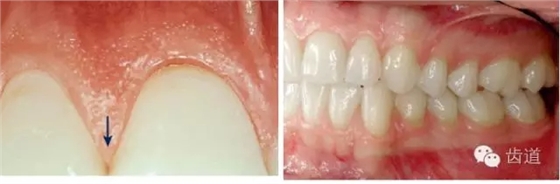

1、口腔衛(wèi)生狀況及局部刺激物(牙菌斑、牙石,不良修復(fù)體)

牙石及不良修復(fù)體

2、牙齦

(顏色、形狀、質(zhì)地、退縮、BOP、PD、附著齦)